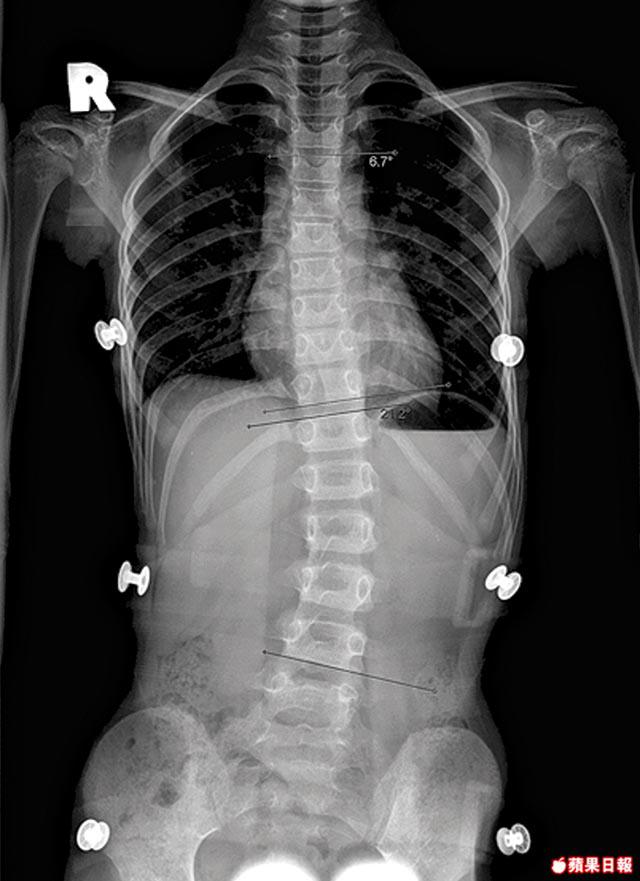

患上脊柱側彎症(Scoliosis)的學童越來越多,據香港衞生署近年調查顯示,患者佔全港學童比率約17%,更有上升趨勢。資深物理治療師黃蓓(Keff)指,脊柱側彎可源於姿勢不良,但亦可來自遺傳,而女性患者較多,原因未明,估計是荷爾蒙或骨質與男性有所差異引致。Keff表示,健康的脊椎,正面看上下成一直線,側面看腰、背應呈流線型曲線,但問題脊椎正面會呈現S或C字形的彎曲。由於此症多發於青春期,年輕患者可趁未造成結構性的變形,多進行脊椎伸展活動及改善日常站姿、坐姿等可望改善情況。

要防止脊柱側彎惡化,着重伸展的普拉提運動(Pilates)能起預防及治療作用。因為Pilates能訓練人體核心肌肉,令其保持正直,減慢脊椎變彎速度;當肌肉夠強健,也有助拉長已扭曲及縮短的脊椎。今次我們請來的小ModelElle,經檢查後發現上半身向右彎,下半身則向左擺,Keff進一步檢查她的腰部及盆骨亦發現兩邊高低不平衡,確定Elle下半身確是向左移位了。然後Keff就為Elle準備了矯形「上身右彎、下身左擺」的運動,而一般人清楚自己脊椎彎向何方,亦可在家進行這些運動,情形就如膠樽被扭埋一邊,向「反方向」鬆開就可改善。

側彎少於20度:會形成高低膊,脊椎兩側肌肉長期處於不平衡而緊張,引致肌肉疲勞。

側彎20至40度:引致胸部變形,兩側肌肉常會抽搐。

側彎大於40度:背部嚴重畸形,若側彎角度惡化將壓迫心臟及肺部影響此等器官功能。